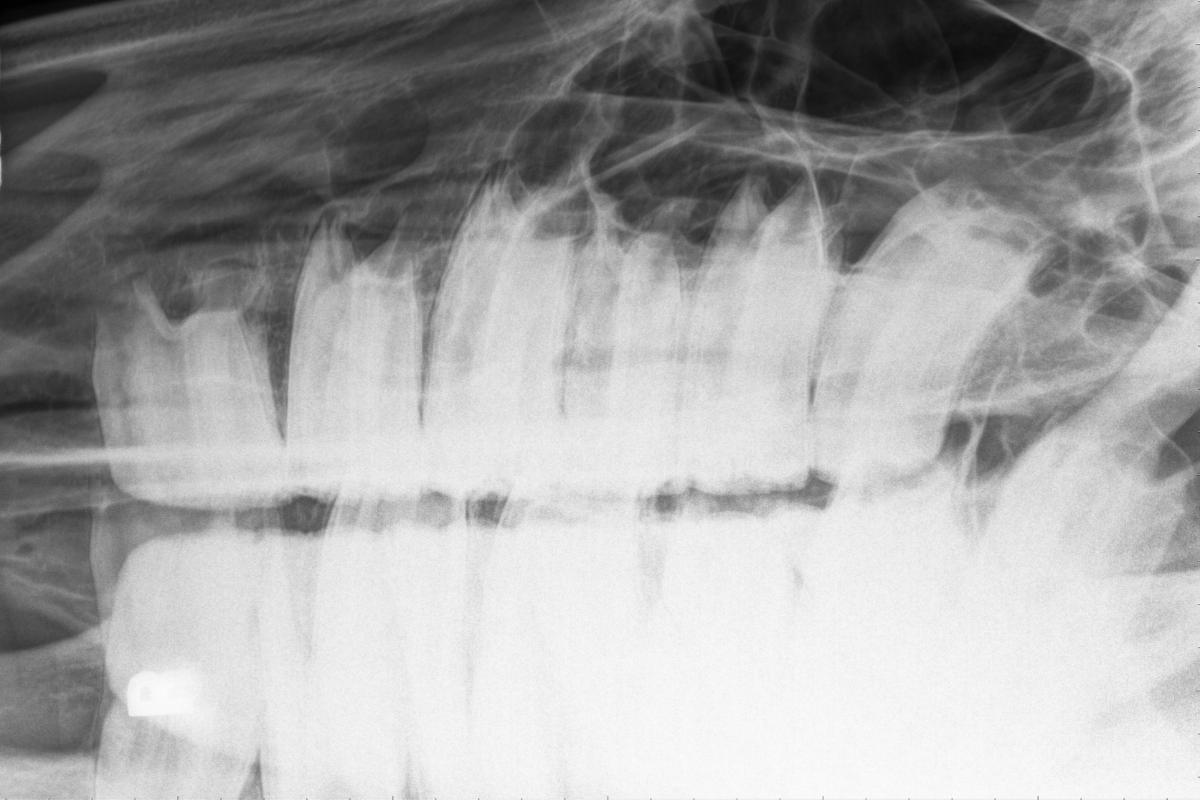

Como hemos mencionado en apartados anteriores, los caballos tienen 4 tipos de dientes: incisivos, caninos, premolares y molares. Cada uno de estos dientes tiene tres partes bien diferenciadas:

- La corona: es la parte visible del diente.

- La raíz: es la parte del diente incluida en el hueso alveolar del maxilar o la mandíbula.

- El cuello: es el límite entre la corona y la raíz.

Tanto la corona como la raíz están constituidas fundamentalmente por dentina. A su vez, la corona está cubierta por esmalte (que es el tejido más duro y mineralizado del organismo) y la raíz está cubierta por cemento (un tejido similar al hueso). La porción central de cada diente (la cavidad pulpar) está ocupada por la pulpa dental, la cual contiene los vasos y los nervios que irrigan e inervan el diente. El aparato que da soporte a cada diente se conoce como periodonto, y está formado por la encía, el ligamento periodontal, el cemento que recubre la raíz del diente y el hueso alveolar.

Aunque todos los dientes tengan una estructura y una composición similar, cada tipo de diente tiene unas características particulares, adaptadas a una función determinada.

- Los incisivos son los dientes encargados de agarrar y cortar el alimento. Son largos y estrechos y tienen el cuello poco marcado. La superficie de oclusión presenta una invaginación, conocida como infundíbulo, la cual se utiliza como indicador para conocer la edad de los caballos.

- Los premolares y molares actúan aplastando y triturando el alimento. Los molares y premolares se confunden con facilidad, puesto que morfológicamente son casi idénticos.